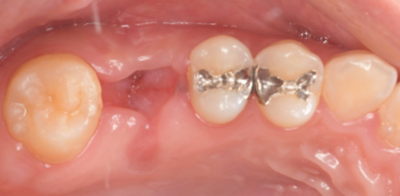

初診時口腔内写真

初診時パノラマX線写真と口腔内写真。

右上6に腫脹と排膿がみられた。